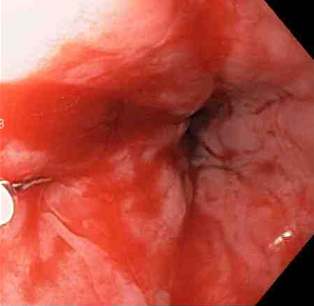

Laceração de Mallory-Weiss

Adrenalina é injetada localmente ao redor do local da laceração de Mallory-Weiss

Do acervo de Juan Carlos Munoz, MD, University of Florida